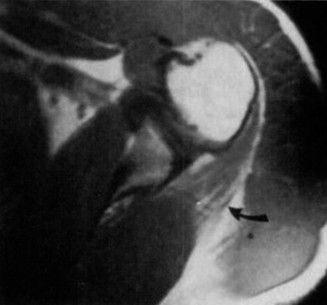

Radiographic Evaluation of the Shoulder

Given the clinical findings of axillary nerve palsy and lateral shoulder contour flattening, a complete trauma series of the shoulder (True AP, Scapular Y, and Axillary lateral views) was mandatory.

The radiographs revealed a displaced, two-part proximal humerus fracture involving the surgical neck (Neer Classification). The humeral shaft was medially translated and apex anteriorly angulated relative to the humeral head. The greater and lesser tuberosities appeared intact on initial plain films. There was no evidence of glenohumeral dislocation on the axillary view, suggesting that the axillary nerve palsy was likely secondary to a traction neurapraxia at the moment of impact, or direct impingement/stretch across the sharp medial osseous spike of the displaced humeral shaft fracture.

A dedicated CT scan of the proximal humerus was also acquired for preoperative templating. This confirmed the Neer two-part surgical neck fracture and ruled out occult tuberosity extensions or articular head splitting components. The medial calcar region demonstrated significant comminution, indicating inherent medial instability that would dictate the choice of fixation construct.